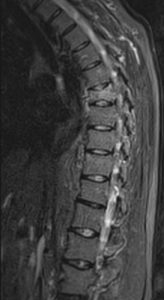

La instrumentación percutánea o “MIS”, en esto último caso, tiene mucho interés porque los pacientes presentan muchos problemas de salud asociados que contraindicarían o por lo menos una cirugía muy agresiva.

La cifoplastia y la vertebroplastia ofrecen resultados inmediatos, con estancia hospitalaria corta además de poder obtener un resultado histopatológico de la lesión (biopsia).